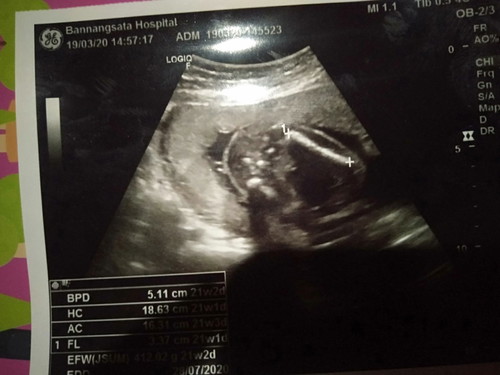

แม่ๆคนไหนซาว์ด แล้วดูยังไงค่ะ ว่า ชายหรือหญิง ค่ะ

ผู้ชายค่ะแม่

ชายค่ะ